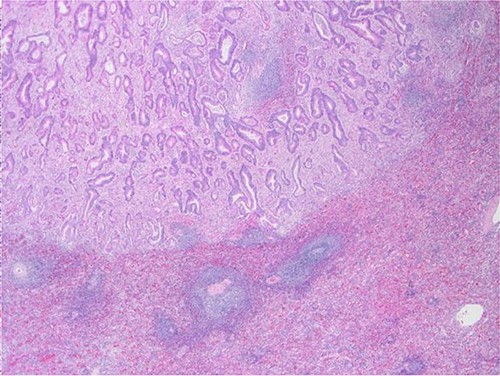

The definitive pathological report revealed adenocarcinoma metastases with morphology and immunophenotype compatible with an intestinal origin, both in splenic parenchyma and in uterine myometrium (see Figs 1–8).

Surgical specimen: splenectomy; macroscopically, neoplastic retraction of the splenic capsule corresponding with a nodular, well-circumscribed, whitish neoplasm, 45 mm in diameter; parenchymatous resection margins are intact.

Surgical specimen: splenectomy; microscopy, HE; spleen parenchyma infiltrated by well-formed neoplastic glandular structures composed of cells with ‘pencillated’ and atypical nuclei, with nucleoli, apoptosis and mitotic figures, consistent with an intestinal origin (metastatic colorectal adenocarcinoma).

Surgical specimen: splenectomy; microscopy, HE; spleen parenchyma infiltrated by well-formed neoplastic glandular structures composed of cells with ‘pencillated’ and atypical nuclei, with nucleoli, apoptosis, and mitotic figures, consistent with an intestinal origin (metastatic colorectal adenocarcinoma).